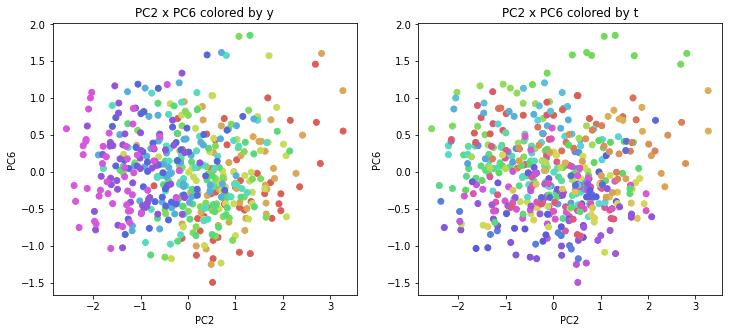

PCAの結果の第n主成分をPCnと表記します。

医療費データの場合と同様に、PCAの結果を見やすく表示するため、seabornのカラーパレットを使って、年月別、都道府県別に色分けして図示してみます(左側が年月別に色分け、右側が都道府県別に色分け)。PC1~PC8まで表示しました。

医療費データの場合ほどはっきりとはしていませんが、PC2が概ね時間の経過を表す成分で、残りの成分が時点によって変わらない地域の特徴を表す成分となっているようです。

また、PC1×PC3を見ると、47沖縄が他の都道府県からかなり離れたところに位置しており、沖縄の地域差が際立っているのが分かります。これは、以前別の記事で年齢階級のない健診データでPCAを実行した場合と似た結果となっています。

今回は、医療費データと同様に、健診データ240次元についてPCAを実行してみました。PCAの結果、医療費データの場合ほどはっきりしとはしていませんが、第2主成分が概ね時間の経過を表す成分で、時間軸に沿った全体的な動き(全国的な動き)を表しており、それ以外の成分が地域の特徴を表す成分で、この10年間あまり変わっていないことがわかりました。